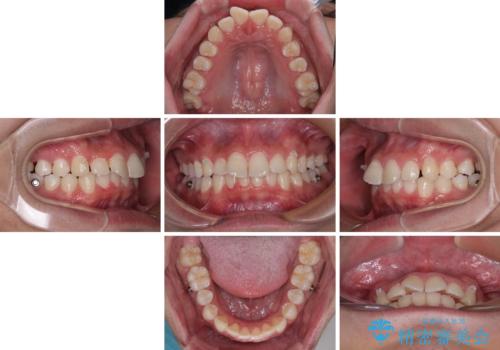

- ディープバイトと上顎前歯の突出、奥歯の咬み合わせを気にして来院された患者様です。

上顎歯列は全体的に前方位にあり、それが原因で深い咬み合わせとなり、突き上げにより上顎前歯が前方に飛び出している状態でした。

また、左右ともに上顎最後臼歯が頬側に転位している鋏状咬合となっていました。